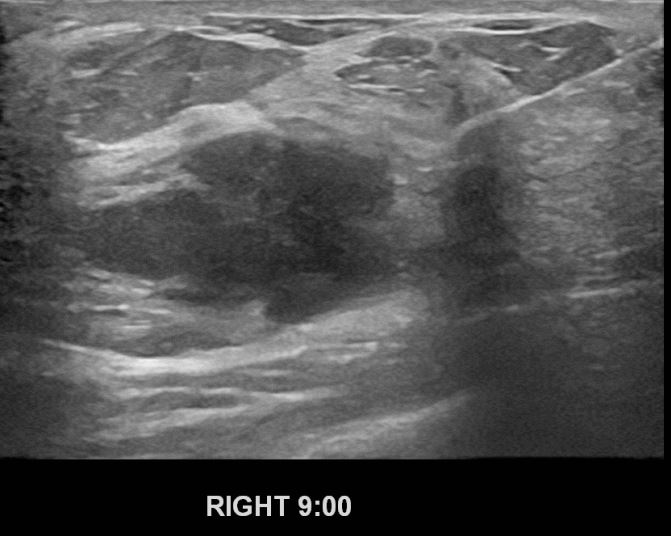

외부검사상 이상소견으로  조직검사위해 내원하신 40대 여성분으로

조직검사결과 유방암 진단되셨습니다